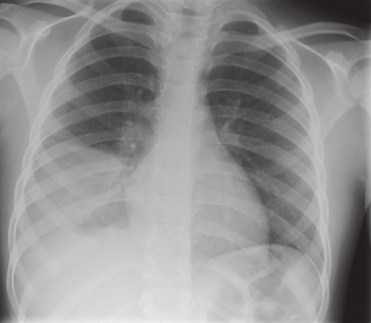

Chẩn đoán Viêm phổi hít phải hay "viêm phổi do rối loạn nuốt" là Hỏi bệnh sử và khám thực thể. Chụp X-quang, chụp cắt lớp vi tính (CT Scan) và xét nghiệm máu thường được chỉ định. Cấy đờm và máu cũng có thể được thực hiện.

Điều trị Viêm phổi hít phải hay "viêm phổi do rối loạn nuốt" là Phân tích khí máu động mạch (ABG), cấy máu, cấy đờm, xét nghiệm máu toàn bộ (CBC), chụp cắt lớp vi tính, chụp X-quang.